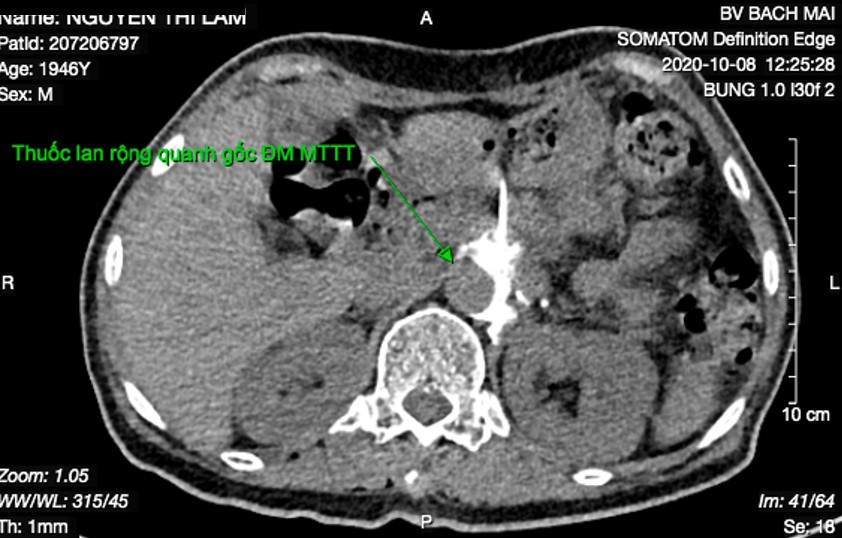

Bơm kiểm tra hỗn hợp thuốc cản quang và gây tê lan quan động mạch chủ bụng